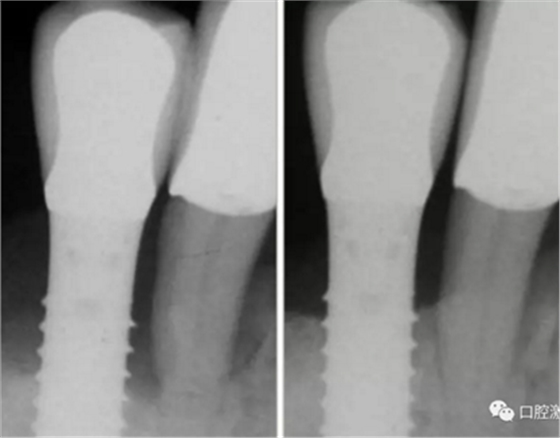

激光非手术种周炎治疗前与治疗后2年的对比